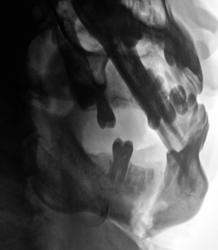

Пациент был направлен в рентгеновский кабинет для рентгенографии нижней челюсти 2 месяца тому с диагнозом "перелом нижней челюсти".

Произведены снимки.

Было высказано предположение о наличии "застарелого перелома" нижней челюсти и наличии остеомиелитического процесса. Пациент был направлен в областное челюстно-лицевое учреждение, где находился на стационарном лечении.